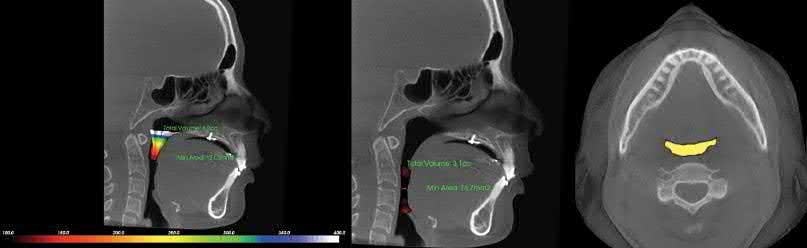

A recent follow‐up study evaluated the relationship between the amount of maxillary arch distalization with palatal anchorage plates and changes in the airway space. Whether the cases were treated with premolar extraction (3.4 mm of the maxillary first molar distalization) or with

non‐extraction (3.2 mm of the maxillary first molar distalization), there were no significant changes in airway volume or minimum cross‐sectional area of the oropharynx after maxillary arch distalization (Figure 1.4d) [15].

Figure 1.4  Comparison between a palatal anchorage plate and buccal TADs [14, 15]. (a) A palatal anchorage plate was placed for maxillary total arch distalization. (b) TADs were placed on the buccal side of the posterior teeth. (c) The palatal anchorage plate group showed greater distalization and greater intrusion with less distal tipping of the maxillary first molar and more extrusion of the maxillary incisor than the buccal TAD group. (d) No significant changes were found in the airway volume or minimum cross-sectional area of the oropharynx after treatment with these two groups.